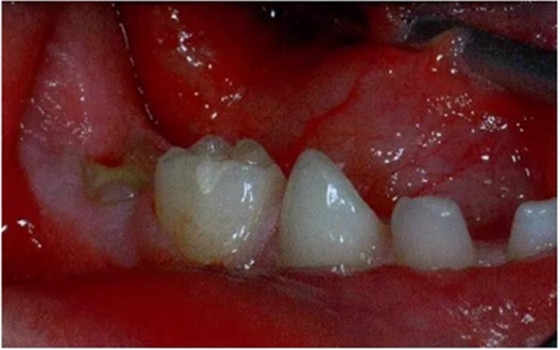

圖1:輕度下沉的臨床像

圖2:中度下沉的臨床像

圖3:重度下沉的臨床像

圖8展示了一張5歲孩子右下第二乳磨牙嚴(yán)重下沉的口內(nèi)像。臨床檢查可見右下第一乳磨牙遠(yuǎn)中傾斜,朝向下沉乳牙。X線片檢查顯示所有恒牙胚都存在(圖9)。無論是臨床還是影像學(xué),都可檢查到有齲齒的存在。鑒于這顆下沉乳牙在年齡較小時(shí)就已經(jīng)非常嚴(yán)重,同時(shí)還患有齲病,因此決定予以拔除。后期在放置間隙保持器的同時(shí)還應(yīng)持續(xù)觀察監(jiān)測(cè)右下第一恒磨牙和第二前磨牙的萌出情況。

圖8:一名五歲患兒右側(cè)下頜第二乳磨牙嚴(yán)重下沉臨床像